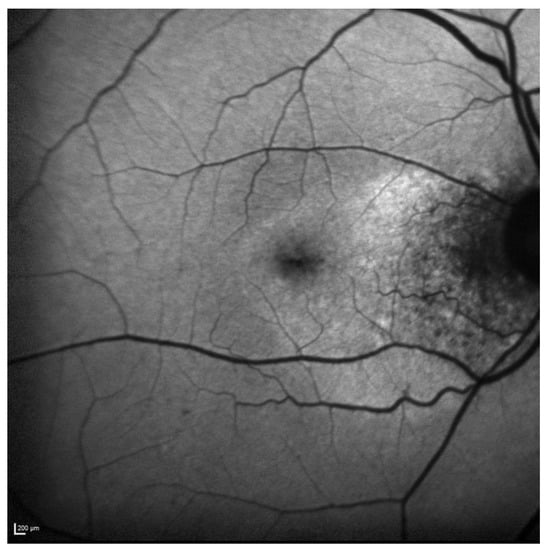

FAF revealed a hypoautofluorescent macular lesion in the left eye (Figure 8).

Figure 8.

Case 6. Heidelberg Spectralis blue autofluorescence shows a left eye macular hypoautofluorescent lesion.

The OCT scan showed a dry macula with drusen in the right eye and a type 1 MNV with PEDs, intraretinal and subretinal fluid, subretinal haemorrhage, and a haemorrhagic BALAD in the left eye (Figure 9A).

Figure 9.

Case 6. (A) Heidelberg Spectralis optical coherence tomography shows a type 1 MNV with fibrovascular pigment epithelial detachment, subretinal and intraretinal fluid, and haemorrhagic BALAD in the left eye. (B,C) Heidelberg Spectralis optical coherence tomography shows a good response after a year and two years of intravitreal anti-VEGF treatment, respectively.

The OCTA scan confirmed the presence of the left MNV.

A T&E regimen with anti-VEGF intravitreal injection therapy was commenced. The patient showed an initial good response to the treatment (Figure 9B). Unfortunately, over the following years, the worsening of the condition was observed despite treatment. Thus, the patient switched to a different anti-VEGF molecule.

To date, the patient is still on treatment. The left BCVA was 0.4 logMAR when last examined. The last OCT scan showed intraretinal fluid and an improved BALAD (Figure 9C).

Figure 10 shows Optos Ultra-widefield colour and autofluorescence imaging of the left eye macular lesion two years after the start of the treatment.

Figure 10.

Case 6. Optos Ultra-widefield colour and autofluorescence imaging of the left eye after two years of intravitreal anti-VEGF treatment, showing a yellowish (A) and hypofluorescent (B) macular lesion. The retinal haemorrhage was fully resolved (A,B).